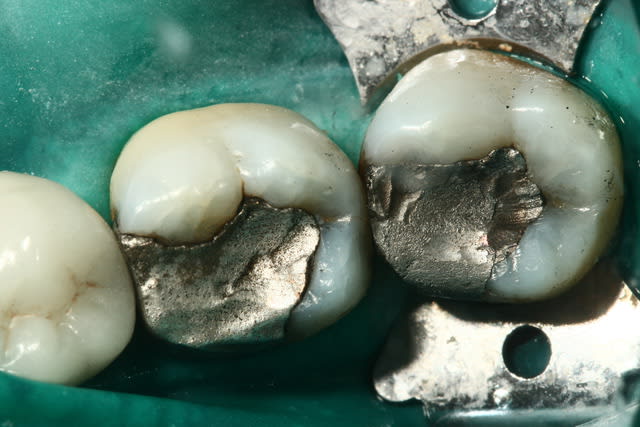

Photo 1. Moi: "Voilà pourquoi il vous faut un onlay."

Photo 3. Le patient: "Ah quand même! Ben on va faire les autres alors!"

Une fois l'onlay unitaire maitrisé,

la prochaine étape, passe "au secteur", et évite les unitaires.

Comme tu as de belles photos d'emsemble, pense global

Tu fais 16 ET 17 ensemble.